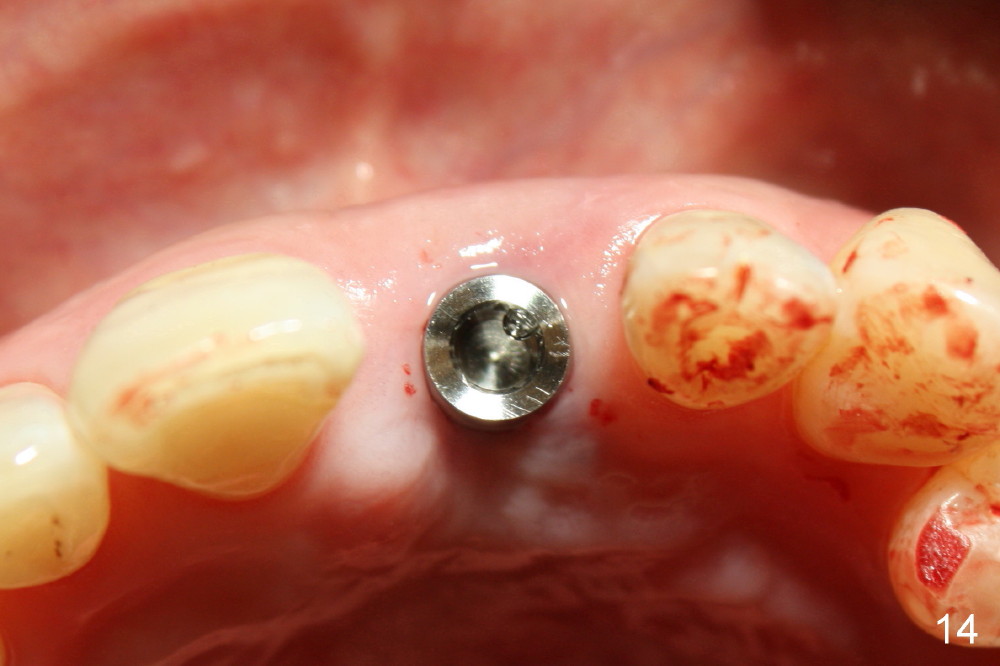

A 60-year-old lady had an abscess mesial to #9 six years ago (Fig.1,2 <), treated as a perio lesion by laser (Fig.3) and osseous surgery without bone graft (Fig.6, followed by CT exam revealing semi-circumferential bone loss (Fig.4,5). When the perio treatment failed, attention was paid to endo aspect (Fig.7-9). In fact the pulp was found to be vital when access to root canal therapy was made. As expected, the treatment failed again. The palatal fistula persisted. The infection was suspected to be a source of remote immediate implant site (#30). The tooth #9 was extracted. It appears that there is a semilunar crack line in the linguomesial root (Fig.12). When the socket healed 2 weeks post extraction (Fig.10), the #30 buccal defect was debrided with bone graft. There was no bone resorption 4 weeks post extraction (Fig.11); a 4.5x17 mm implant was placed (Fig.13-15). An immediate provisional was fabricated (Fig.16-18). Fig.19,20 were taken 3 months post implantation and 7 months post cementation, respectively. Dense bone forms around the implant coronally 4 years 5 months post cementation (Fig.21), while the gingiva is healthy palatally (Fig.22) and buccally (Fig.23).